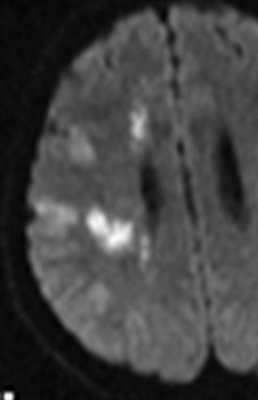

МРТ головного мозга. Аксиальная Т2-взвешенная МРТ. Кровоизлияние в мозжечок.

МРТ головного мозга. Диффузионно-взвешенная МРТ последовательность. ОНМК в острой стадии вследствие вазоспазма.